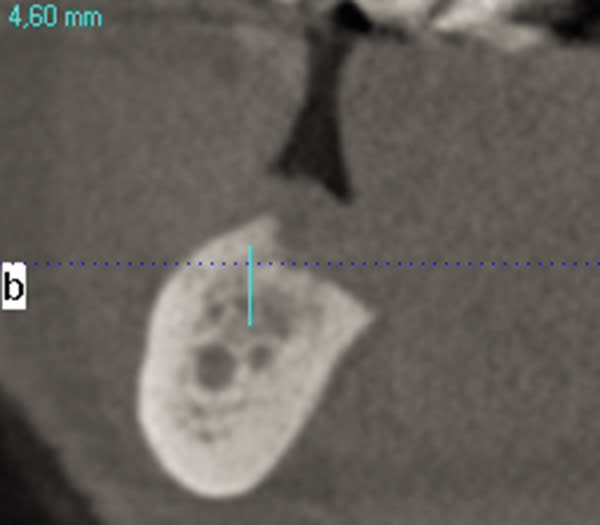

Severe Crestal Atrophy

The patient presented with the posterior mandible showing severe atrophy (Figure 16). The computed tomography (CT) scan showed 3.6 mm and 4.6 mm of available bone height with a failing premolar (Figure 17 and Figure 18). To regain function, the premolar was removed, and two Ultra-Short implants were placed in the molar region and splinted together (Figure 19 through Figure 22).